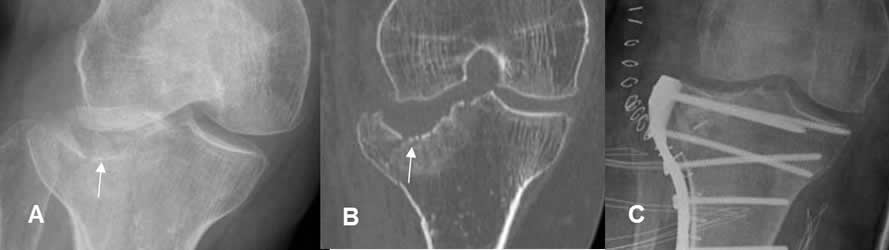

Fig 106. Placa de compresión.

A: Rx AP y B: TAC reconstrucción coronal. Fractura deprimida y conminuta en el platillo tibial lateral.

C: Rx AP. Reducción abierta y fijación con placa de compresión y tornillos.